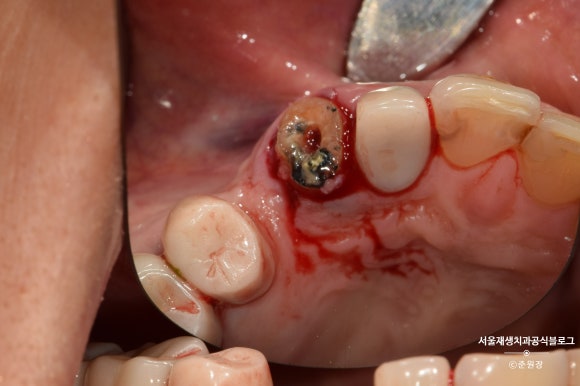

깊은 충치로 머리가 간신히 남은 치아입니다.

머리도 얼마 안남았는데...

크라운을 씌우기 불안할 만큼 잔존치질이 부족합니다.

냅다 발치한 사진을 먼저 보여드리게 됐네요^^

핀셋에 간신히 잡혀 있는 부분이 머리입니다.

혈액이 묻어있는 부분은 모두 뿌리입니다.

이제 이해가 되실겁니다.

뿌리만 남은 치아라는 걸요...^^;;

이미 신경치료가 잘 되어 있던 치아라서,

혹시 모를 재감염을 방지하기 위해

뿌리 끝을 약간 잘라냈습니다.